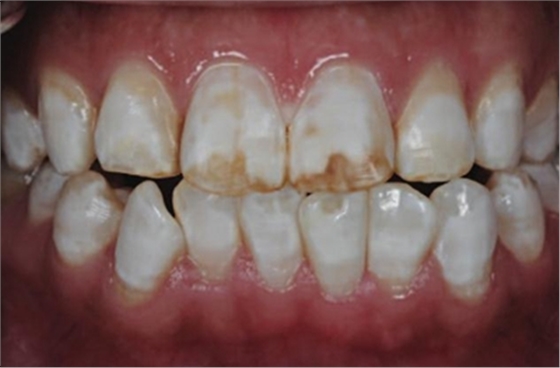

在診室內(nèi)漂白的同時(shí)聯(lián)合運(yùn)用家庭漂白。在使用8支10%過氧化脲凝膠 (Ultradent Products) 后,患者很滿意漂白效果。

5、由于氟斑牙存在釉質(zhì)礦化不全等問題,家庭漂白兩周后,使用標(biāo)準(zhǔn)的樹脂滲透技術(shù) (Icon, DMG Products, Hamburg. Germany) 來預(yù)防釉質(zhì)齲。最后,徹底改變患者的前牙美學(xué),并在一年后仍保持穩(wěn)定。